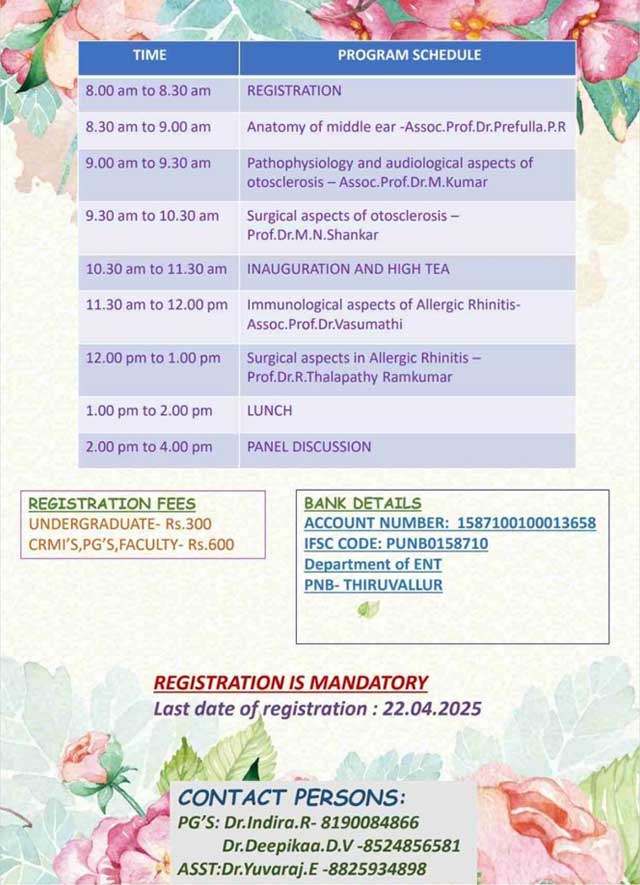

ENT CME ON OTOSCLEROSIS AND ALLERGIC RHINITIS: 24/04/2025

Topic |

Date |

| CEP- Otosclerosis and Allergic Rhinitis | 24-04-2025 |